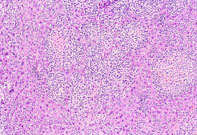

Histiocytic sarcoma (Kupffer cell sarcoma) is a multicentric neoplasm of mice that frequently involves the liver. It is uncertain whether the cells are derived from Kupffer cells or from other histiocytes. The malignant cells grow along the sinusoids and vessels, efface the normal architecture of the hepatic lobules, and sometimes form nodules.

Extensive hepatic involvement by malignant histiocytic cells.

Low and high magnifications of a histiocytic sarcoma with a nodular growth pattern in the liver.

Giant cell formation in a histiocytic sarcoma.